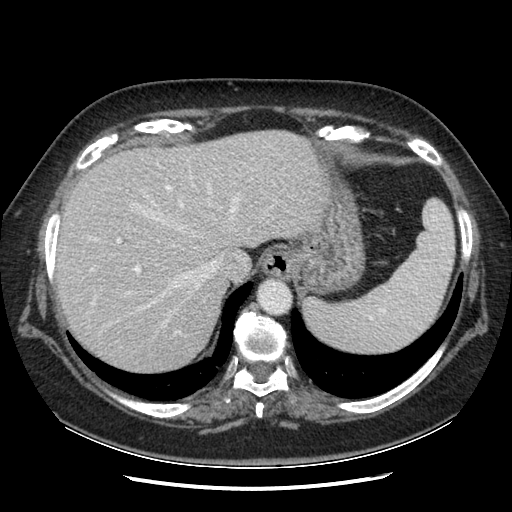

Original NATIVE CT scan (input)

Mediastinum window (WL 40, WW 400 β†’ Low βˆ’160, High +240)

Reconstructed NATIVE CT scan (cycle consistency)

Original VENOUS CT scan

Generated VENOUS CT scan (A→B translation)